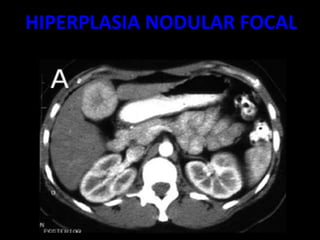

HIPERPLASIA NODULAR FOCAL